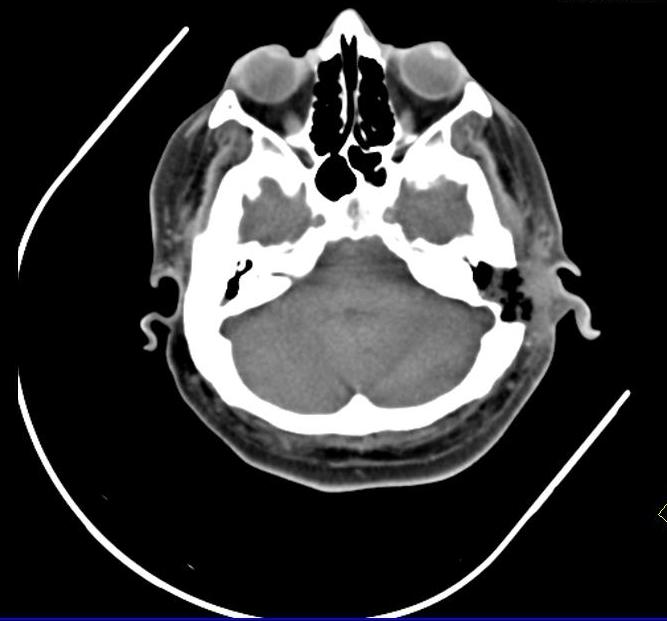

A new case of a 50-year-old female who presented with left otorrhagia caused by an internal carotid aneurysm is reported. No medical history of tinnitus, vertigo, otalgia or otorrhea. Middle ear surgery was effective in resolving bleeding and did not cause any permanent neurological deficit. High resolution computed tomography angiography is the technique of choice and, in some cases, can be complemented with a magnetic resonance angiography. Misdiagnosis of the internal carotid artery aneurysm may lead to serious morbidity because of bleeding or vascular occlusion.